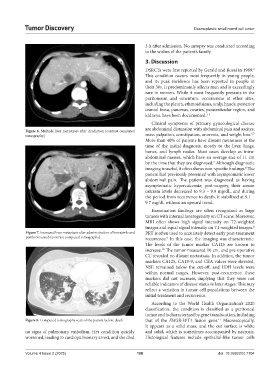

Figure 6. Multiple liver metastases after irradiation (contrast computed

6,7

tomography) mass palpation, constipation, anorexia, and weight loss.

More than 40% of patients have distant metastases at the

time of the initial diagnosis, mostly to the liver, lungs,

bones, and lymph nodes. Most cases develop as intra-

abdominal masses, which have an average size of 11 cm

by the time that they are diagnosed. Although diagnostic

3

imaging is useful, it often shows non-specific findings. The

8